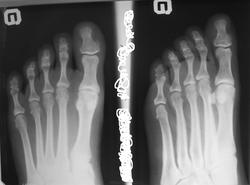

Пол пациента: Женский пол Тип патологии: Врожденная патология Область исследования: Скелетно-мышечная система Методы исследования: Rg Молодая женщина пришла на снимок. указывая на резкую болезненность в основание ногтевой фаланги 1 пальца стопы. ID:22391 Сб, 28/07/2012 - 14:46 #1 Dr.Yllich Не на сайте Был на сайте: 1 год 4 месяцев назад Зарегистрирован: 01.05.2011 - 22:52 Публикации: 1196 Экзостоз? С уважением. Ильич. Сб, 28/07/2012 - 18:18 #2 Глазков Игорь А... Не на сайте Был на сайте: 9 месяцев 2 недели назад Зарегистрирован: 19.12.2008 - 20:41 Публикации: 1597 похоже на это. Прийди к Себе Сб, 28/07/2012 - 22:31 #3 И.Бондаренко Не на сайте Был на сайте: 2 дня 12 часов назад Зарегистрирован: 13.09.2011 - 22:55 Публикации: 9206 +1 Вс, 29/07/2012 - 22:02 #4 Катенёв Валенти... Не на сайте Был на сайте: 7 лет 2 недели назад Зарегистрирован: 22.03.2008 - 22:15 Публикации: 54876 По всей видимости, такой экзостоз и клинику может дать.

Экзостоз?

По всей видимости, такой экзостоз и клинику может дать.